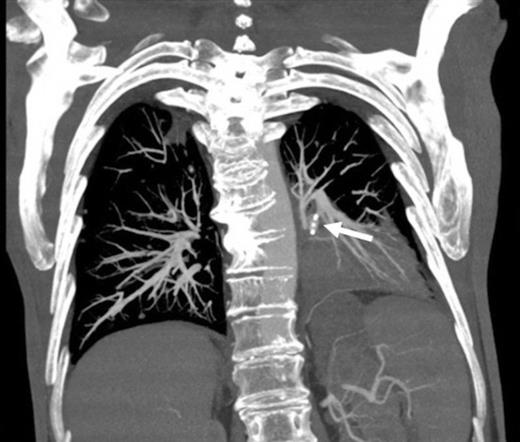

Coronal CT image in arterial phase demonstrating a 28mm diameter left lower lobe pulmonary artery aneurysm in association with a fluid collection

Three days later he presented with significant haemoptysis. A CT pulmonary angiogram (CTPA) demonstrated an increase in size of the PAA from 14mm to 28mm (Figure 1) diameter. A radiology opinion was sought and the patient transferred to the angio-suite for intervention.